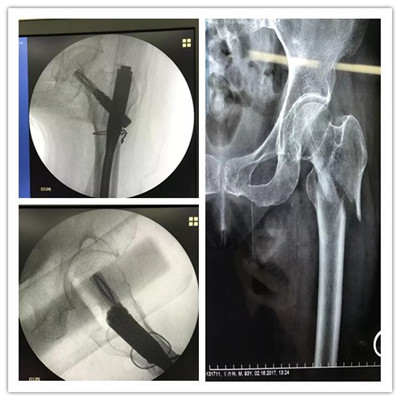

近日,舟山廣安骨傷醫(yī)院成功為一位95歲高齡的老太太實施股骨粗隆骨折微創(chuàng)手術(shù)。術(shù)后一天就可以床上活動。

老太太今年已經(jīng)95歲高齡了,一周前在家不慎滑倒摔傷,疼痛難忍,不敢活動,遂由家人急送至舟山廣安骨傷醫(yī)院,經(jīng)拍片檢查確診為左股骨粗隆粉碎性骨折。

廣安醫(yī)院關(guān)節(jié)科副主任羅軍稱,老太太不但高齡,還患有心臟病,低蛋白血癥,重度骨質(zhì)疏松癥,手術(shù)麻醉風(fēng)險極高,但若保守治療需要長期臥床,且不說骨折能否愈合,致命的臥床并發(fā)癥就極難避免。經(jīng)過醫(yī)院多科室會診,在腰部麻醉下,羅軍副主任為老太太實施了股骨髓內(nèi)釘(PFNA)微創(chuàng)手術(shù)。術(shù)后各項生命體征平穩(wěn),術(shù)后第一天就可床上活動,目前可以持助行器下地活動了。